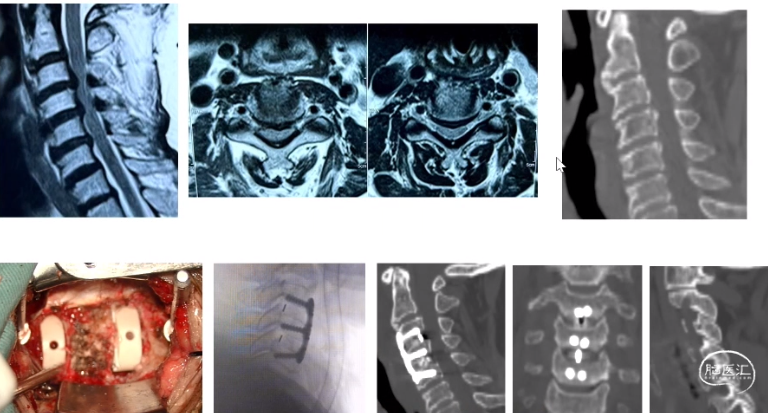

后纵韧带骨化:椎体次全切ACCF

如何防治椎体塌陷?

如何预防和治疗脑脊液漏?

椎体及骨化后纵韧带复合体

整体迁移融合技术ACAF

后路单开门

后路单开门:门轴断裂

后路减压固定融合